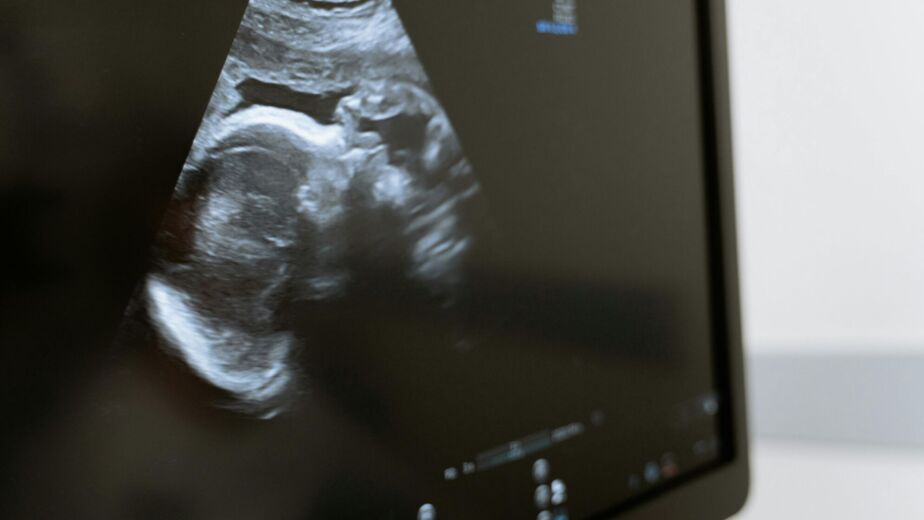

A gender reveal scan is an ultrasound that focuses on identifying the baby’s sex. It uses the same safe ultrasound technology as routine NHS scans. Our sonographer looks carefully at the genital area to determine whether you are expecting a boy or a girl. At MotherScan, we aim to make this a joyful experience. You will not only receive confirmation of your baby’s gender but also have the chance to see clear images of your baby in the womb.

Most clinics, including MotherScan, offer gender scans from 16 weeks onwards. At this stage, the baby’s external genitalia are usually developed enough to provide reliable results. Before 16 weeks, the accuracy decreases because the structures may look similar in both boys and girls.

From 16 weeks, gender scans are generally 95-99% accurate. Accuracy depends on the baby’s position and how clearly the genital area can be seen. Sometimes, if the baby is curled up or facing away, the sonographer may invite you back for a free repeat scan to confirm the result. It is important to remember that no scan is 100% guaranteed, but with skilled sonographers and high-quality equipment, accuracy is very high.

3D and 4D scans can provide beautiful, lifelike images of your baby, but when it comes to determining gender, 2D ultrasound is usually the clearest method. That is why sonographers primarily use 2D mode to confirm gender, sometimes switching to 3D or 4D for keepsake images.